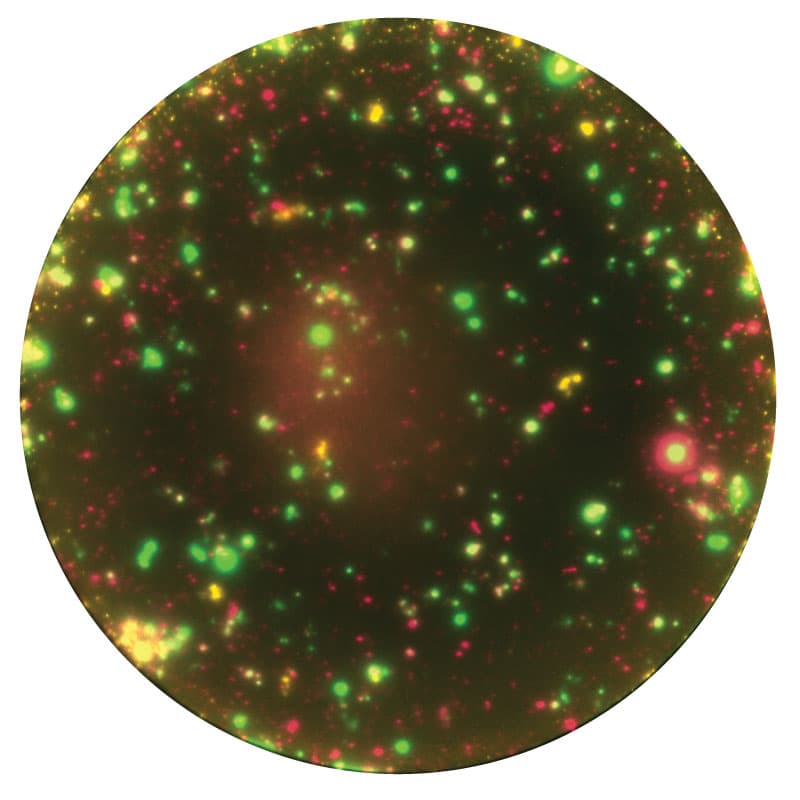

Different secretory profiles provide insights into the CTL or T helper cell response.

Polyfunctional T cell profiling

FluoroSpot's advanced multiplexing allows for the detailed analysis of secretory profiles of individual immune cells, providing key insights into immune system dynamics, such as Th1 or Th2 responses, or cytotoxic T lymphocyte activity. This detection of multiple cytokines enables a more nuanced understanding of immune cell function and the orchestration of immune responses, crucial for refining strategies in vaccine research and the development of novel immunotherapies. The assay can facilitate a deeper characterization of the immune response, leading to enhanced immune profiling.